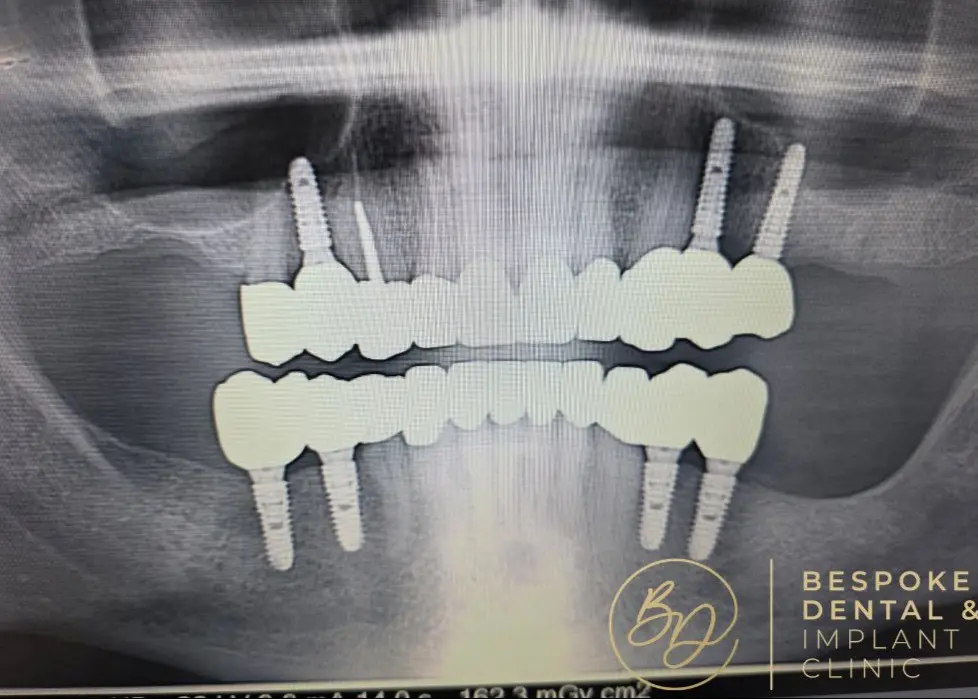

Full mouth

dental implants

Single Jaw

from £12,000

Full Mouth Implants

from £22,000

All Inclusive:

Surgery

Implants

IV Sedation

Zirconia Implant Bridges

5 Years Warranty